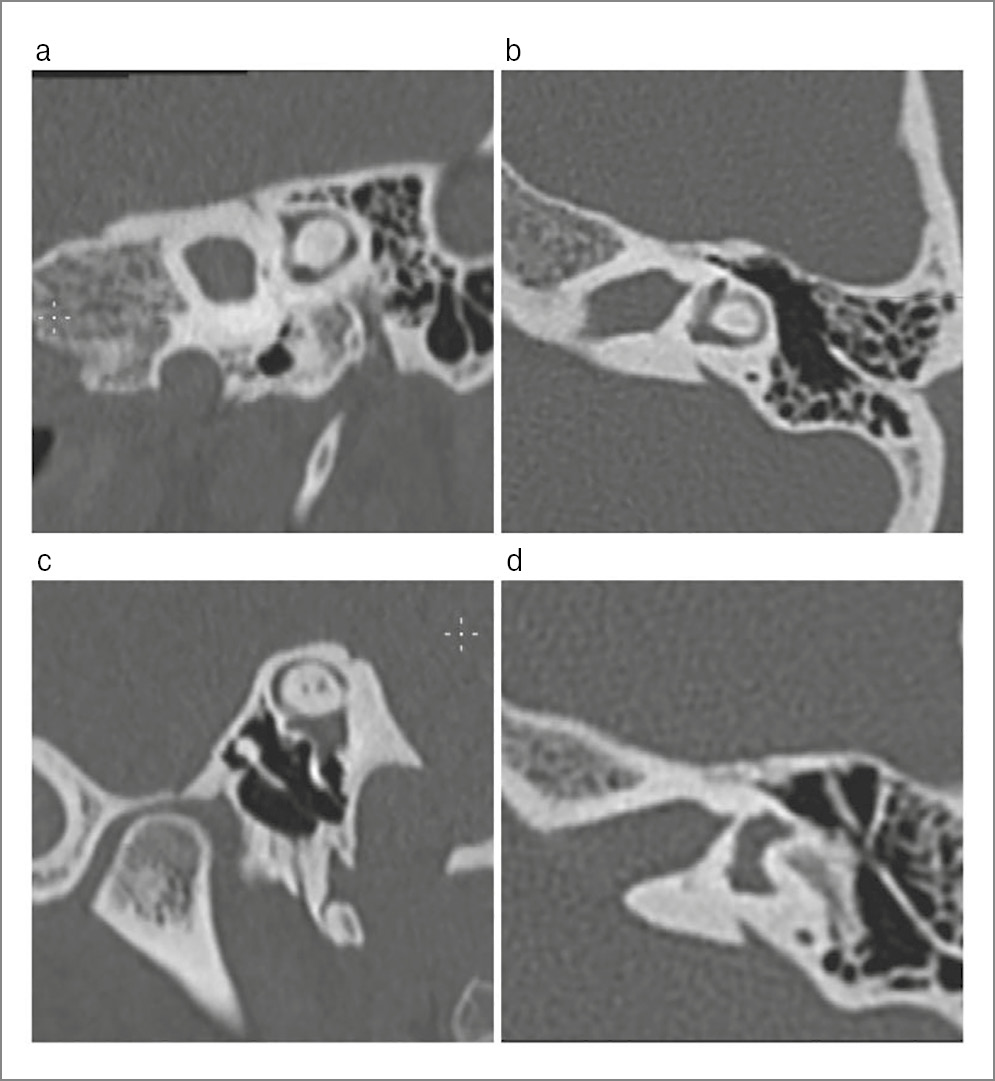

In March 2023, patient L., 24 years old, presented at the St. Petersburg Research Institute of ENT with hearing loss in both ears, more on the left, and periodic mixed tinnitus. She had these symptoms for 2 years. According to the patient, she had no previous history of chronic or acute ear diseases; her family history is unremarkable. From 2010 to 2016, she was followed up by an epileptologist for an epilepsy episode; in 2016, she was withdrawn from the follow-up. Somatically, she had an arach-noid retrocerebellar cyst and a congenital anomaly of the urinary system, left kidney duplication. Other findings were unremarkable. The otoscopic pattern was normal. When conducting acoustic impedance measurement, the type A tympanogram on both sides was recorded; the stapedial reflex-es on both sides were absent. Tonal audiometry corresponded to a grade 2 mixed hearing loss on the left, with the Carhart notch at 2000 Hz and grade 1 conductive hearing loss on the right (Fig. 1). When examined with a 128 Hz tuning fork, the lateralization of sound in the Weber test spread to the left ear, the Rinne’s, Federicci’s and Gellé tests were negative on both sides. CT (Fig. 2, 3) and virtual CT endoscopy of the ME (Fig. 4) showed no changes in the ME and IE. The configuration of the semicircular canals, the vestibular aqueduct, and the perilymphatic duct were unremarkable. TB CT showed no demineralization of the labyrinth bone capsule, gross deformations of the AO chain, or abnormalities in the structure of the ME and IE.

Fig. 2. MSCT scans of the left TB showed the normal structures of the vestibule: a – normal dimensions and absence of bone wall defects in the middle and apical turns of the cochlea; b – normal dimensions and absence of wall defects in the perilymphatic duct and the basal turn of the cochlea; c – normal dimensions of the vestibular aqueduct; d – normal dimensions and absence of bone capsule defects in the vestibule.